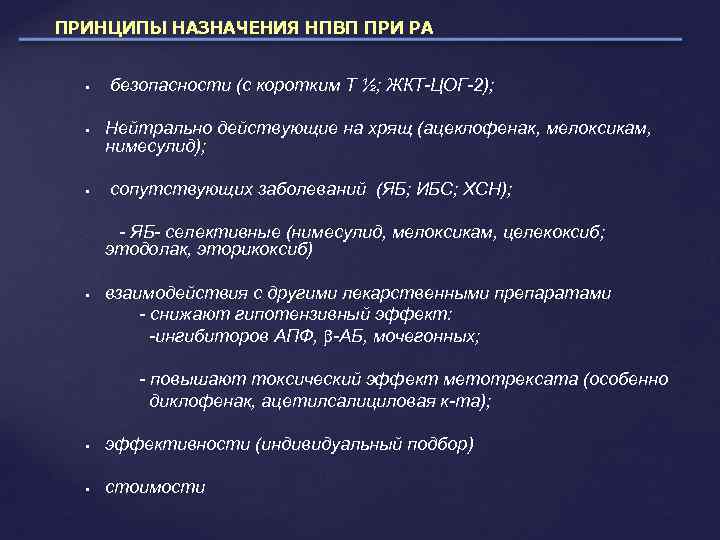

ПРИНЦИПЫ НАЗНАЧЕНИЯ НПВП ПРИ РА безопасности (с коротким Т ½; ЖКТ-ЦОГ-2); Нейтрально действующие на хрящ (ацеклофенак, мелоксикам, нимесулид); сопутствующих заболеваний (ЯБ; ИБС; ХСН); - ЯБ- селективные (нимесулид, мелоксикам, целекоксиб; этодолак, эторикоксиб) взаимодействия с другими лекарственными препаратами - снижают гипотензивный эффект: -ингибиторов АПФ, -АБ, мочегонных; - повышают токсический эффект метотрексата (особенно диклофенак, ацетилсалициловая к-та); эффективности (индивидуальный подбор) стоимости

ПРИНЦИПЫ НАЗНАЧЕНИЯ НПВП ПРИ РА безопасности (с коротким Т ½; ЖКТ-ЦОГ-2); Нейтрально действующие на хрящ (ацеклофенак, мелоксикам, нимесулид); сопутствующих заболеваний (ЯБ; ИБС; ХСН); - ЯБ- селективные (нимесулид, мелоксикам, целекоксиб; этодолак, эторикоксиб) взаимодействия с другими лекарственными препаратами - снижают гипотензивный эффект: -ингибиторов АПФ, -АБ, мочегонных; - повышают токсический эффект метотрексата (особенно диклофенак, ацетилсалициловая к-та); эффективности (индивидуальный подбор) стоимости